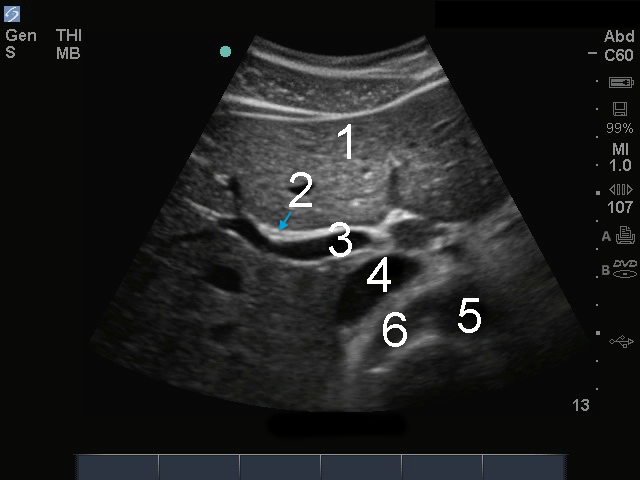

1. Foie

2. Voie biliaire principale (VBP)

3. Veine porte (VP)

4. Veine cave inférieure (VCI)

5. Aorte

6. Artère rénale droite (ARD)